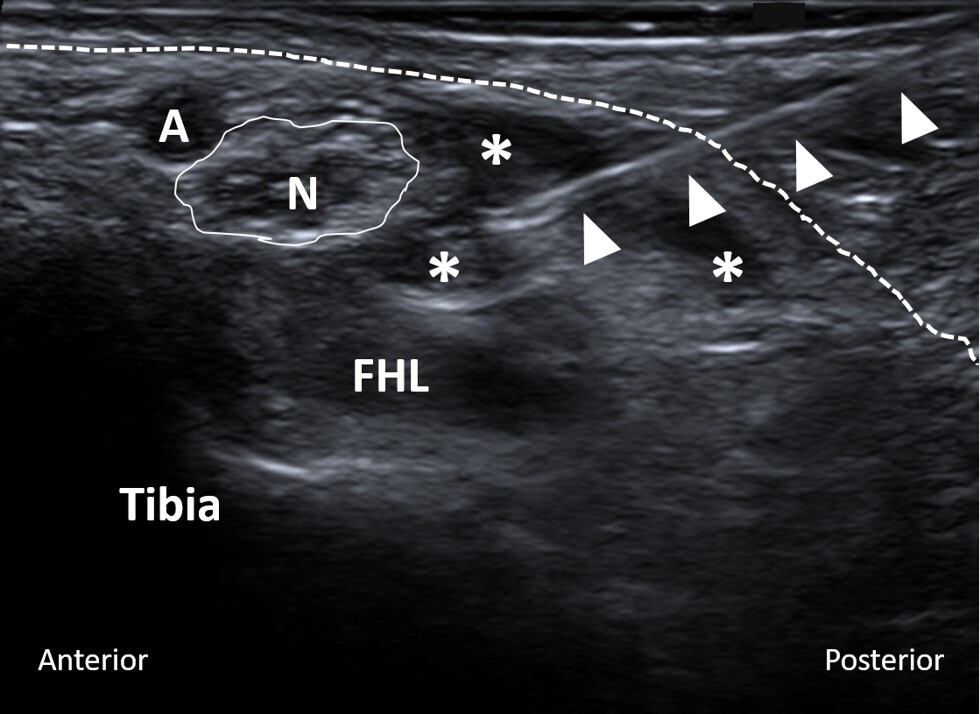

All US-guided tarsal tunnel injections were performed by experienced musculoskeletal radiologists at our institution. The level of pain around the involved foot and tarsal tunnel area before the injection was recorded on a scale from zero to ten. Utilizing local anesthesia and a sterile technique, a 25-gauge needle was advanced into the tarsal tunnel under US guidance (Figure 1). Subsequently, 0.5 cc of 0.25% bupivacaine mixed with 0.5 cc (20 mg) of triamcinolone (40 mg/mL) was injected. After the injection, the level of pain was recorded once again.